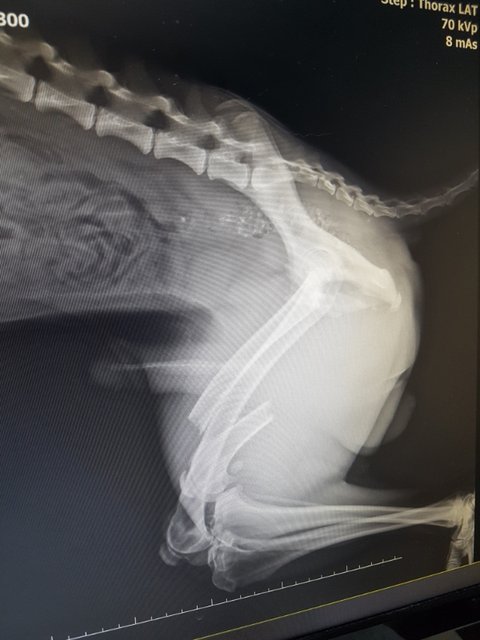

역시나 다발성 골절..

골반뼈와 오른쪽 뒷다리가 부러져 있었습니다